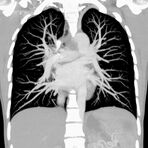

Thorax (Brustkorb)

• Entzündungen oder Tumore des Mediastinums und der Lunge

• Lungenembolie- Diagnostik

• hochauflösende Darstellung des Lungenparenchyms zur Abklärung chronischer interstitieller Erkrankungen wie z. B. Fibrosen, Emphysem, Bronchiektasen